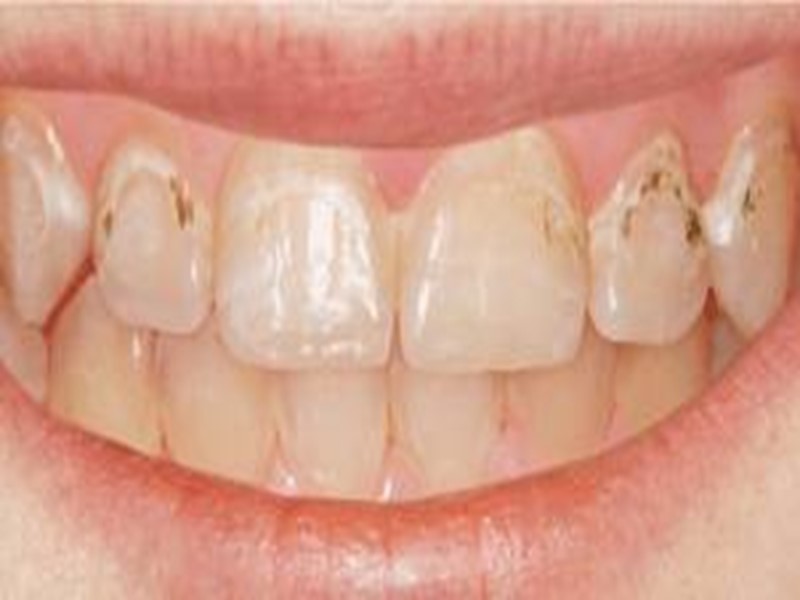

Начальный кариес дифференцируют: флюорозом (пятнистой формой) системной гипоплазией (пятнистой формой) местной гипоплазией (пятнистой формой).

Дифференциальная диагностика кариеса в стадии пятна с гипоплазией и флюорозом Общее: наличие пятен на эмали, эстетический дефект

Поверхностный кариес дифференцируют с: Системной гипоплазией (бороздчатая форма) Флюорозом (эрозивная форма) Эрозией эмали Клиновидным дефектом Кислотным некрозом

Дифференциальная диагностика поверхностного кариеса с гипоплазией и флюорозом Общее: наличие дефекта твердых тканей в пределах эмали, эстетический дефект